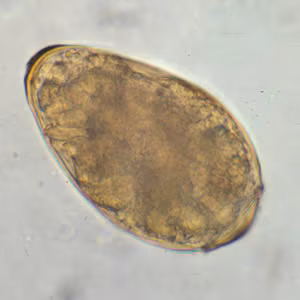

Eggs of Paragonimus kellicotti.

Diagnosis is based on microscopic demonstration of eggs in stool or sputum, but these are not present until 2 to 3 months after infection. (Eggs are also occasionally encountered in effusion fluid or biopsy material.) Concentration techniques may be necessary in patients with light infections. Biopsy may allow diagnostic confirmation and species identification when an adult or developing fluke is recovered.